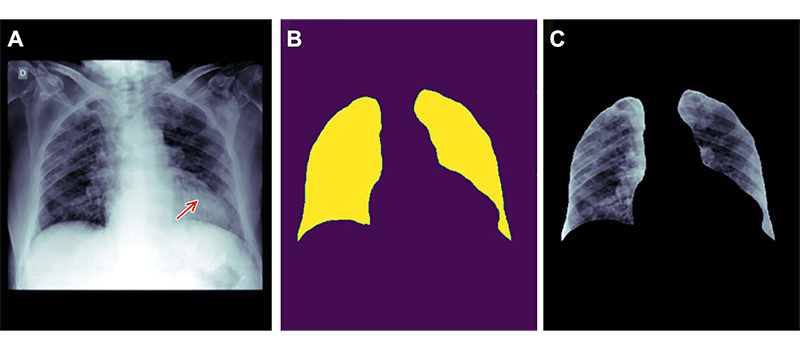

Рис. 4 Эриксон

Пример того, как неправильное удаление признаков из данных изображения может привести к систематической ошибке. (A) Рентгенограмма грудной клетки пациента мужского пола с пневмонией. (B) Маска сегментации легкого, созданная с использованием модели глубокого обучения. (C) Рентгенограмма грудной клетки обрезана на основе маски сегментации. Если кадрированную рентгенограмму грудной клетки отправить в следующий классификатор для обнаружения уплотнений, то уплотнение, расположенное за сердцем, будет пропущено (стрелка, A ). Это происходит из-за того, что удаление первичного признака с использованием модели сегментации было недействительным и без необходимости удаляло часть легкого, расположенную позади сердца.